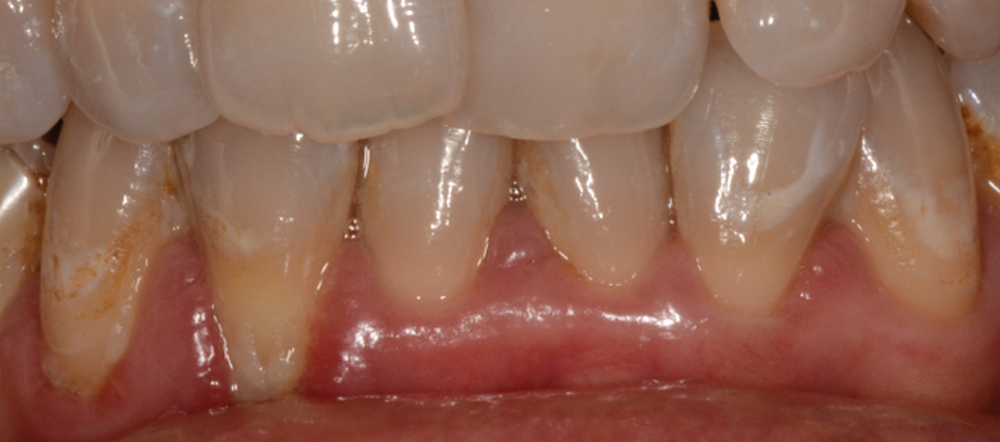

Professeur et chef de service du département de parodontologie et actuellement directeur opérationnel de l’école de médecine dentaire de l’université de Berne, en Suisse, le Pr Sculean est actuellement répertorié comme l’expert le mieux coté en parodontologie dans le monde1. Il est l’auteur du livre Periodontal regenerative therapy consacré aux techniques régénératives contemporaines dans le traitement des défauts osseux et des tissus. Par sa compréhension de l’anatomie du parodonte et des phénomènes de cicatrisation biologique des plaies, sa maîtrise des matériaux régénératifs et des techniques chirurgicales, il nous propose des paradigmes de traitement efficaces et prédictibles. L’objectif est de donner un aperçu des possibilités et des limites de la couverture des récessions en prévention avant ou après un traitement orthodontique. L’utilisation de techniques de greffes tunnelisées permet une couverture prévisible et une augmentation de l’épaisseur des tissus pour les récessions gingivales simples et multiples, tout en assurant une stabilité à long terme. Anton Sculean nous propose une approche clinique rigoureuse et efficace, richement illustrée, qui renouvelle notre collaboration interdisciplinaire avec la parodontologie. Un rendez-vous à ne pas manquer !

Quelle insatisfaction et quelle déception de constater, en cours ou à l’issue d’un traitement orthodontique, la fragilisation du parodonte, voire l’apparition d’une récession gingivale !

C’est à ces questions que nous permettront de répondre les deux premiers conférenciers, parodontologistes : le Dr Béatrice Straub nous présentera le renfort parodontal minéralisé, technique qu’elle a développée et pratique depuis de nombreuses années, pour éviter les préjudices des mouvements orthodontiques à risque, notamment lors des décompensations préchirurgicales (fig. 1a-d) ; le Pr Anton Sculean abordera le thème des greffes, avec leurs indications, les différentes techniques à privilégier et illustrera ses propos par de nombreux cas cliniques aux résultats esthétiques impressionnants.